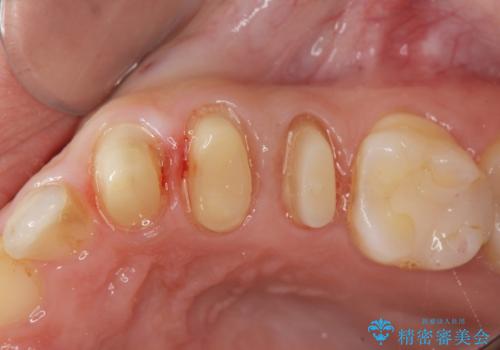

- 歯ぐきの腫れや、歯の内部が黒く見えることからの虫歯の治療を求めて来院されました。

虫歯が大きかったことから、神経の温存はできたものの歯ぐきよりも深い虫歯の問題を解決するため、部分矯正治療を併用したセラミック治療を行うこととしました。

当初、歯ぐきよりも深い虫歯の存在や、歯のポジションに問題がありましたがマルチブラケットを用いた部分矯正で行うことで歯の挺出同時に適切な位置へと歯を移動させ、歯周環境を整えたセラミック治療を行うことができました。